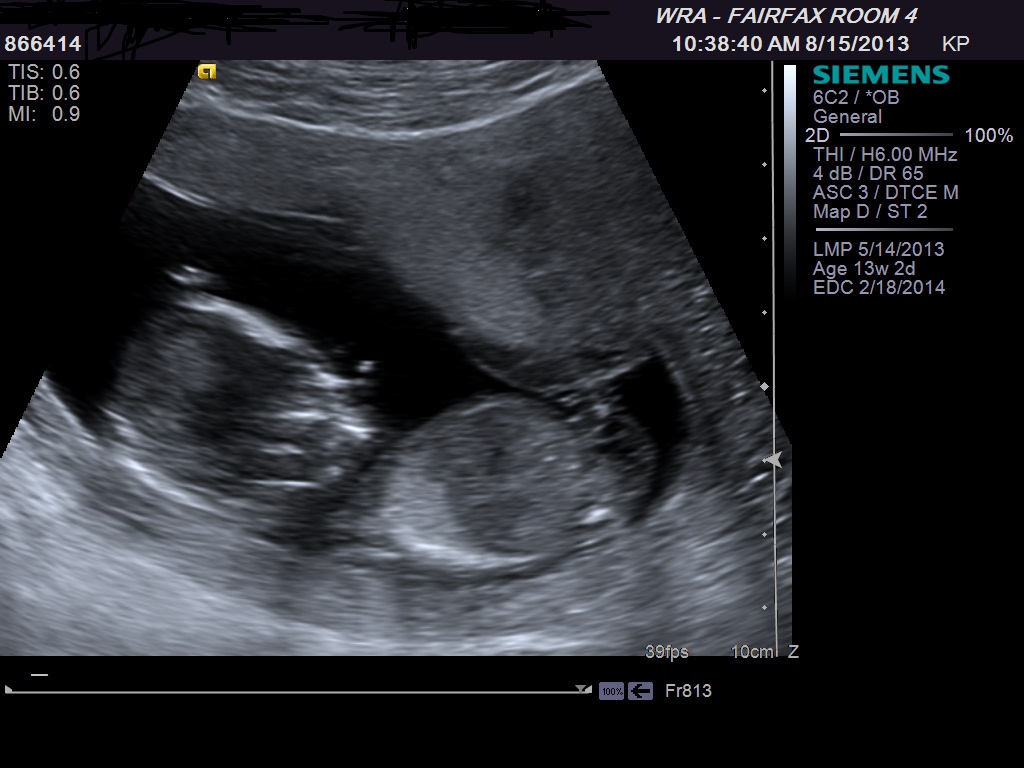

ultrasound 13 weeks is it boy or girl

Attachment 13976

When nub is easy to find